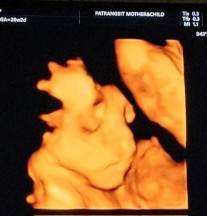

ก่อนหน้านี้ น้องน้ำหนักเกินเกณฑ์มาตลอด เมื่อวานไปซาวด์ 4D มา คุณหมอบอกน้องน้ำหนักต่ำกว่าเกณฑ์ 28W หนัก 905 กรัม เอง แม่มีเรื่องเครียดๆด้วยเลยอาจจะกระทบน้อง แม่ๆบำรุงเพิ่มน้ำหนักน้องยังไงกันบ้างค่ะ